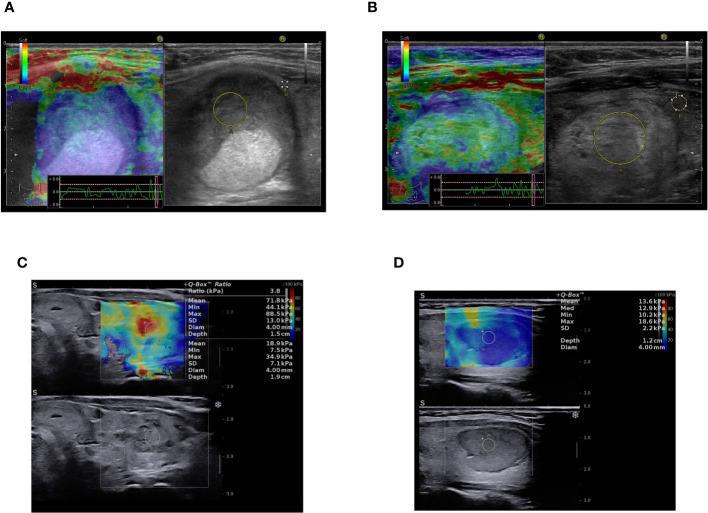

We evaluated ninety-seven consecutive cases with Bethesda category IV results on FNA by using conventional B-mode ultrasound, qualitative strain or shear-wave elastography (Hitachi Preirus Machine, Hitachi Inc., Japan and Aixplorer Mach 30 Supersonic Imagine, Aix-en-Provence, France) and all nodules were classified according to the ACR TI-RADS system. Conventional ultrasound was used to categorize the nodules as potentially malignant based on the following features: hypoechogenicity, inhomogeneity, a taller than wide shape, irregular margins, presence of microcalcifications, an interrupted thyroid capsule and suspicious cervical lymph nodes. Elastography classified nodules with increased stiffness as suspicious for malignancy.

We considered pathology results as the gold standard diagnosis, finding that 32 out of 97 nodules were carcinomas (33%) and 65 out of 97 were benign nodules (67%). The benign group included twenty cases of non-invasive follicular thyroid neoplasm with papillary-like nuclear features (NIFTP). Finally, we compared ultrasound data with pathology results, which showed that nineteen out of the 32 malignant nodules presented with increased stiffness on elastography (p=0.0002). On conventional ultrasound, we found that microcalcifications (p=0.007), hypoechogenicity and irregular margins (p=0.006) are features which can distinguish between benign and malignant nodules with statistical significance.

Integrating elastography as a parameter of the ACR TI-RADS score in the evaluation of Bethesda category IV nodules showed a sensitivity of 90.62% in detecting thyroid cancer cases (p=0.006). We can conclude that elastographic stiffness as an addition to high risk features observed on conventional ultrasound improves the detection of malignant nodules in cases with Bethesda IV cytology.